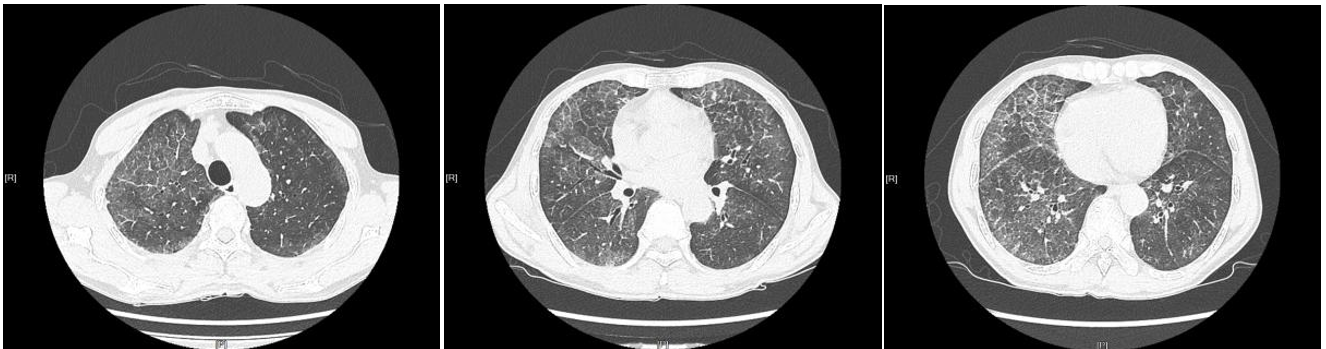

治疗前胸部CT:两肺多发磨玻璃阴影,典型的铺路石症

治疗后两肺渗出阴影明显吸收